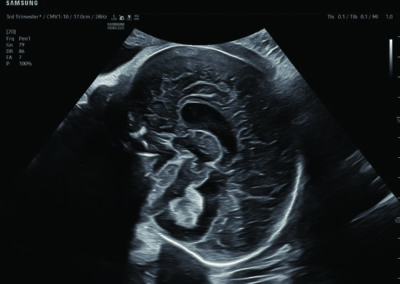

Comprehensive, advanced and expert MFM care for high-risk pregnancies